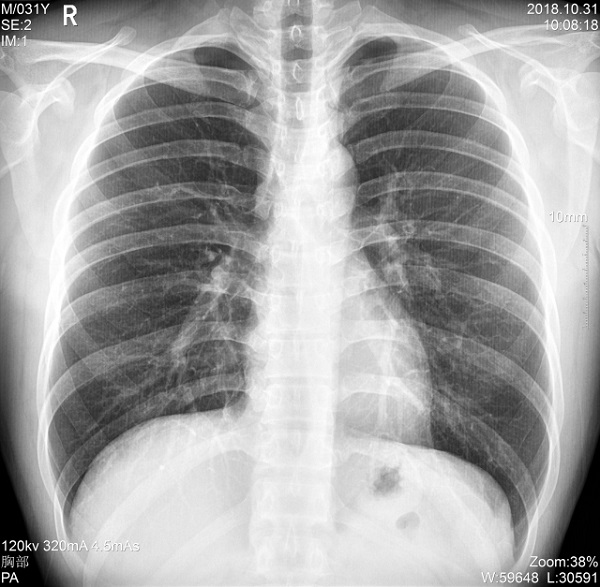

二、1ms 短時曝光 定格心肺運動瞬間影像

PLX5500系列移動DR能夠在1ms的曝光時間內(nèi)輸出足量的X射線,獲取清晰圖像。特別適用于拍攝肺炎、塵肺病、肺結(jié)核等難以憋氣的患者,避免了因患者肺部呼吸運動而產(chǎn)生的運動偽影的影響,瞬間定格清晰圖像,以供醫(yī)生準(zhǔn)確診斷。

三、支持高千伏攝影 肺部紋理更有層次

PLX5500系列移動DR的可調(diào)千伏達(dá)到150kV,在達(dá)到一定高電壓后,與骨骼相重疊的軟組織或骨骼本身的細(xì)小結(jié)構(gòu)及含氣的管腔等,均可清晰顯示。